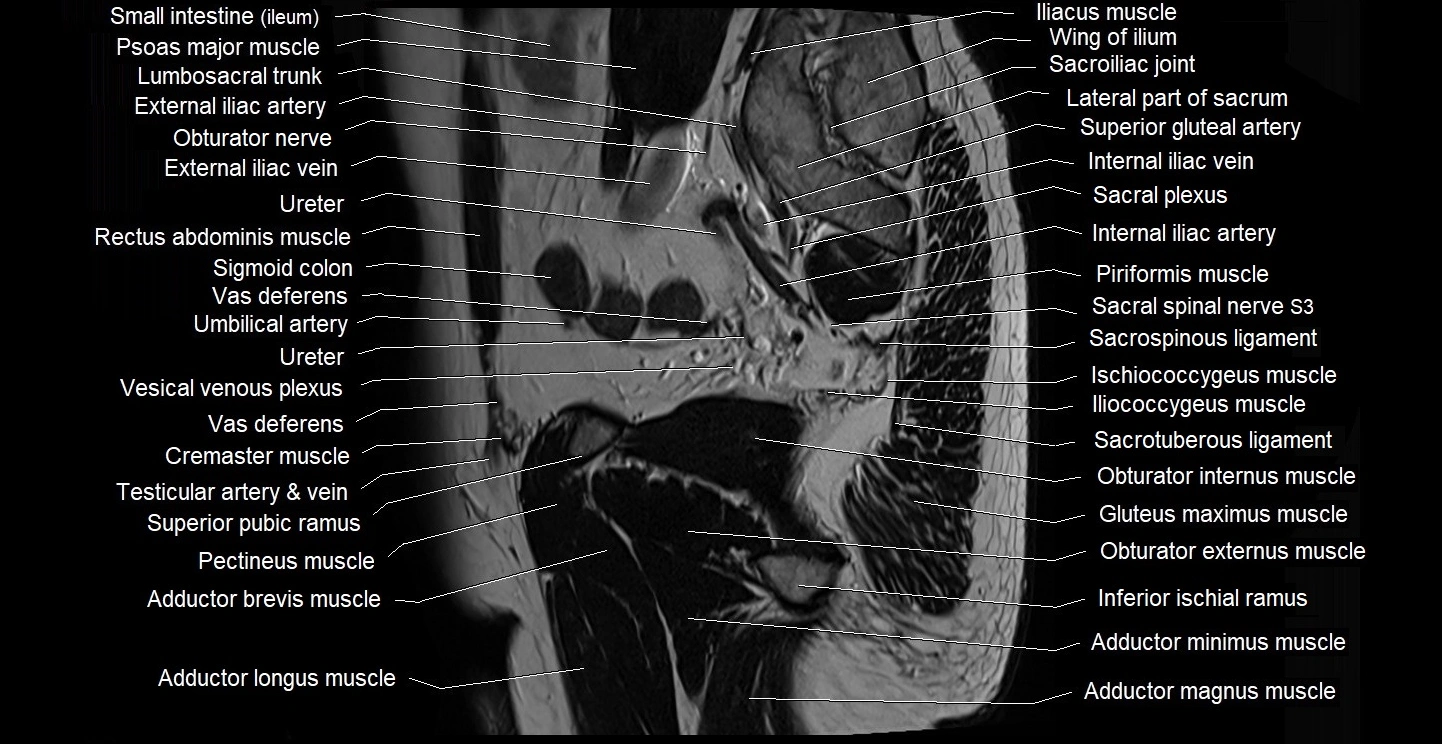

- Adductor brevis muscle

- Adductor longus muscle

- Adductor magnus muscle

- Adductor minimus muscle

- External iliac artery

- External iliac vein

- Iliococcygeus muscle

- Inferior pubic ramus

- Internal iliac artery

- Internal iliac vein

- Ischiococcygeus muscle

- Lumbosacral trunk

- Obturator externus muscle

- Obturator internus muscle

- Pectineus muscle

- Piriformis muscle

- Sacral plexus

- Sacroiliac joint

- Sacrospinous ligament

- Sacrotuberous ligament

- Sigmoid colon

- Superior pubic ramus

- Vas deferens